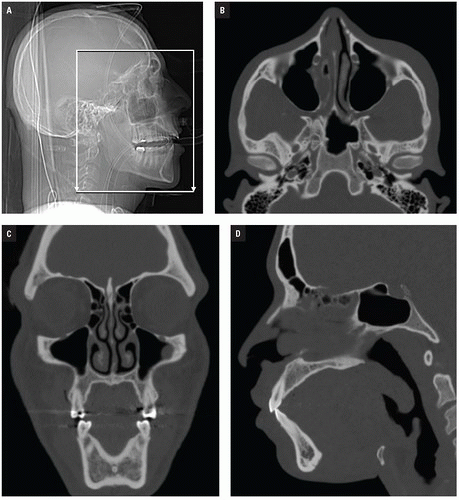

Maxillofacial Tumor Detection - CT images, 3D Deep Learning